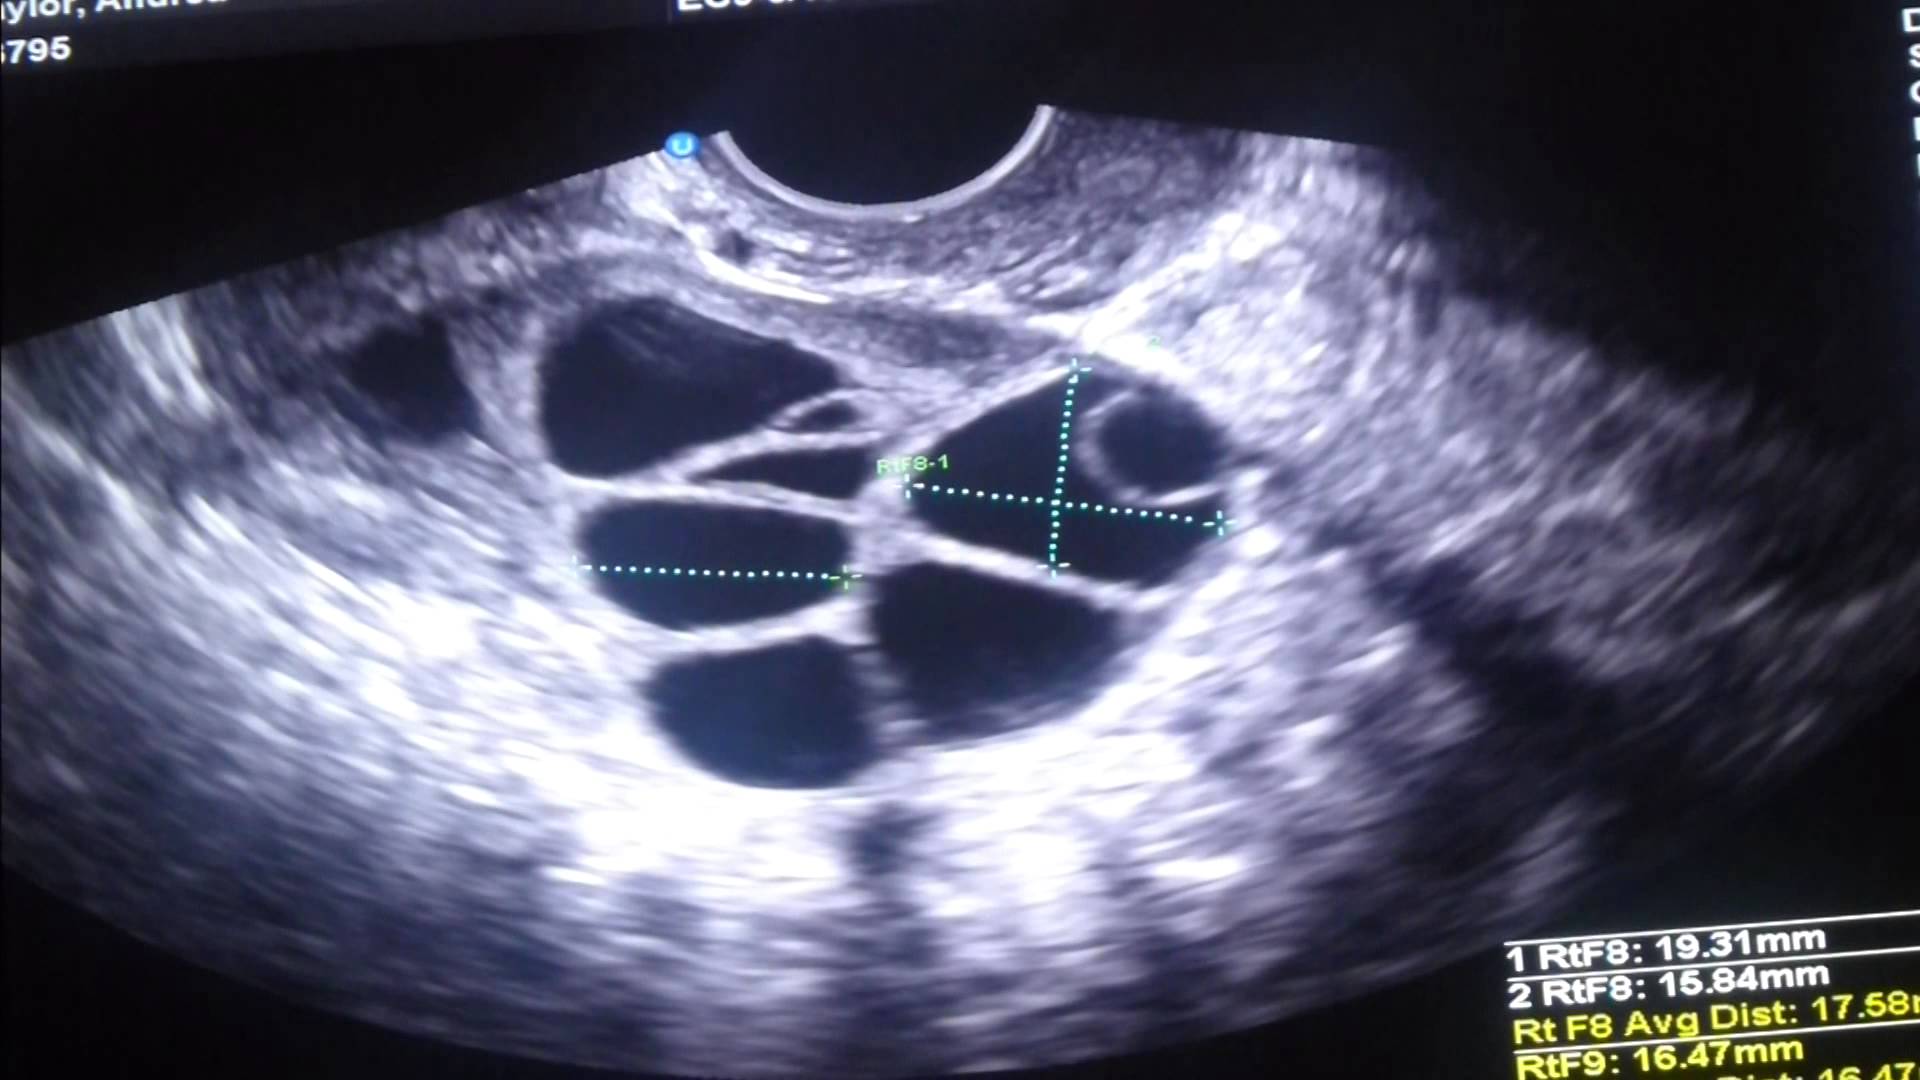

Прогрес се наблюдава и в ултразвуковата визуализация и използването на лека упокойка по време на пункцията, при която се извличат яйцеклетките от яйчниците. Преди се е използвал по-инвазивен лапароскопски метод.

Фоликули под ултразвук